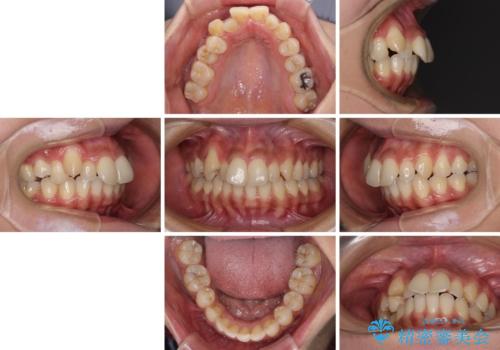

- 八重歯と上下前歯のでこぼこを気にして来院された患者様です。

上下前歯部叢生のスペース獲得のため、上下顎左右小臼歯各1歯(計4本)を抜歯して、ワイヤー装置にて矯正治療を行うこととしました。

上下の正中位置が大きくずれていたため、上下正中が合わないまま終了することが予想されましたが、思っていた以上にスムーズに歯が移動し、満足いただける仕上がりとなりました。